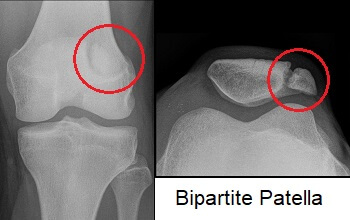

무릎이나 다른 뼈에서도 골절과 혼동하지 말아야할 것들이 몇가지 있는데 골이 fused 되지 못할 때 이러한 증상이 있을 수 있습니다.

대부분 보존적인 치료를 하며, 통증이 심하거나 생활에 지장이 있는 경우 부골 제거술을 시행해 볼 수 있습니다. (부착된 인대 들도 함께 제거될 수 있으므로, 수술시 인대 부분의 생역학을 잘 고려해야합니다.)